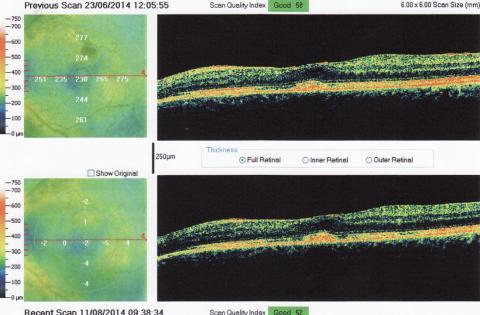

Poškozená sítnice

Pro větší náhled klikněte na obrázek

Dobrý den, aktuálně beru léky (dlouhodobě) Medrol 4mg a Sandimun 150mg, pro léčení nespecifikoveného autoimunitnho onemocnění které mi opakovaně "napadá" sítnici záněty. Aktuálně mě nejvíc trápí levé oko (viz snímek z OCT) 1) Od snížení Medrolu pod 16mg (cca před 4 měsíci) mě trápí nějaké nervové dráždění levého oka, které jak sem vypozoroval bylo "vyprovokované" při obou návštěvách na očním kdy mi rozkapávali oči a dívali se na sítnici. Než sem mi to po předminulé návštěvě uklidnilo trvalo to skoro měsíc ale měl sem klid až do další oční kontroly kdy to začalo znova. Můj oční doktor mi řekl že to může být způsoběno tím jak se oční specialista dívá na sítnici krom toho přístroje ještě čočkou kterou přikládá těsně před oko a to co mě dráždí je rohovka. Mě to ale připadá že mě to dráždí až někdě vzadu jak je sítnice nebo jěště dál když s okem nehýbu tak je to celkem v klidu a jek jím pohnu tak to je jako by mi někdo přejel přes nervy, a když je to opradvu hodně silné tak mi při tomto cuká celé oko a trá mi to s obrazem na který se dívám, ale když se dívám do zrcadla tak zornička se nechýbe, jednou to došlo tak daleko že mě to "vytřelovalo" až do uší a měl sem s toho závratě. Byl sem i na MR a nemám RS 2) Je možné odstranit nebo snížit jejich vnímání i jinou metodou než vitrektomii kterou bych mohl podstopouti i když trpím na chronické záněty sítnice 3) Když mám po poslední velké atatce (v 10/2013) v zorném nějaká slepá místa, je možné s tím něco dělat nebo zlepšít vidění nějakou operací ?